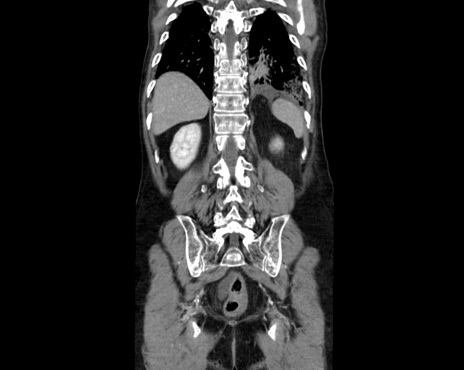

症例26(冠状断像)

【症例】80歳代男性

【主訴】嘔吐

【現病歴】昨晩2回嘔吐あり、今朝になっても嘔吐あり。来院。

【既往歴】胃潰瘍

【身体所見】意識清明、BT 37.6℃、BP 166/95mmHg、HR 100bpm、SpO2 97%、腹部:平坦・軟、腸蠕動音聴取良好、圧痛なし。

【データ】WBC 21900、CRP 1.4